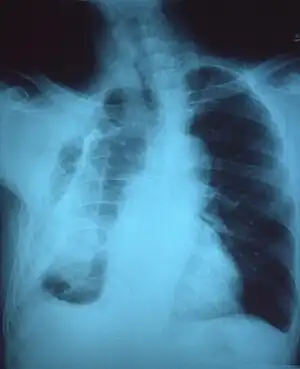

A fibrothorax can typically be diagnosed by taking an appropriate medical history in combination with the use of appropriate imaging techniques such as a plain chest X-ray or CT scan.[3] These imaging techniques can detect fibrothorax and pleural thickening that surround the lungs.[7] The presence of a thickened peel with or without calcification are common features of fibrothorax when imaged.[3] CT scans can more readily differentiate whether pleural thickening is due to extra fat deposition or true pleural thickening than X-rays.[3]

If a fibrothorax is severe, the thickening may restrict the lung on the affected side causing a loss of lung volume.[7] Additionally, the mediastinum may be physically shifted toward the affected side.[3] A reduction in the size of one side of the chest (hemithorax) on an X-ray or CT scan of the chest suggests chronic scarring.[6] Signs of the underlying disease causing the fibrothorax are also occasionally seen on the X-ray.[6] A CT scan may show features similar to those seen on a plain X-ray.[7] Lung function testing typically demonstrates findings consistent with restrictive lung disease.[6]

Extensive left-sided fibrothorax

Chest radiograph displaying inhomogeneous opacification of the left half of the chest that is fibrothorax